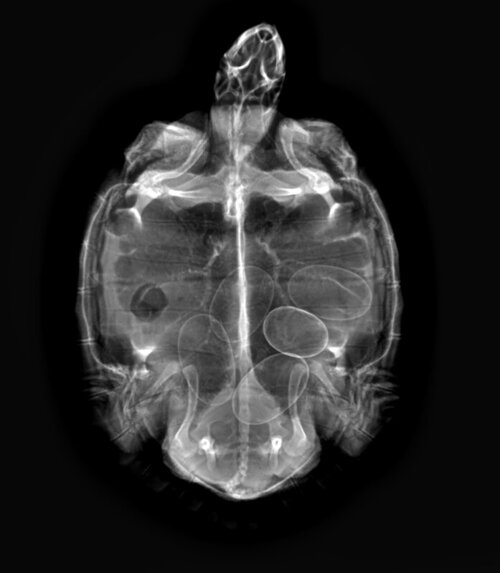

СергейР Ваше имя: Сергей Локация: Ижевск Опубликовано: 17 февраля 2022 Автор Опубликовано: 17 февраля 2022 3 часа назад, moth сказал: а рентген то сделали? Рентген не делали. Зачем и в какой плоскости? Разве панцирь прозрачен для рентгена?

Гость Pashtetreal Опубликовано: 17 февраля 2022 Опубликовано: 17 февраля 2022 @СергейР чтобы знать сколько яиц. Черепаху на спину и держите. Да, рентген пробивает

Консультанты moth Ваше имя: Мария Локация: Москва Опубликовано: 17 февраля 2022 Консультанты Опубликовано: 17 февраля 2022 @СергейР конечно прозрачен. Чтобы увидеть сколько яиц, какой они формы, чего вообще ждать. У неё дистоция, без рентгена Вы понятия не имеете вышли все яйца или они где-то там застряли в яйцекладе и гниют. Я вообще в шоке с таких ветеринаров, кто просто так от балды уколол окситоцин и пусть оно там само как-то.

СергейР Ваше имя: Сергей Локация: Ижевск Опубликовано: 20 февраля 2022 Автор Опубликовано: 20 февраля 2022 Добрый день. Рентген показал наличие 5 яиц. Врач сказал, что черепахи могут длительное время яйца откладывать. Назначил: кальция глюконат 1 мл, ультрафиолет, температура не ниже 25°С. Через 2 недели на приём. 18.02.2022 в 20:09, moth сказал: У самки такие проблемы из-за отсутствия уф лампы и гаммаруса в рационе. А в памятке написано: Нельзя: ..., гаммарус, ... ?